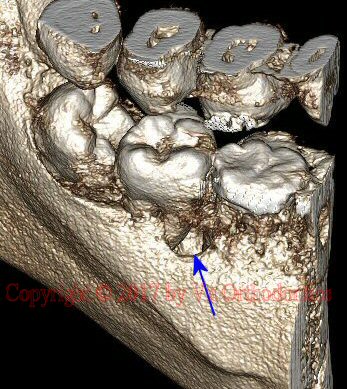

Example 2: RCT (root canal therapy)

Fig. 6 2D view of 3D structure (lingual view), showing bone defect, between lower left 1st and 2nd molars (blue arrow)